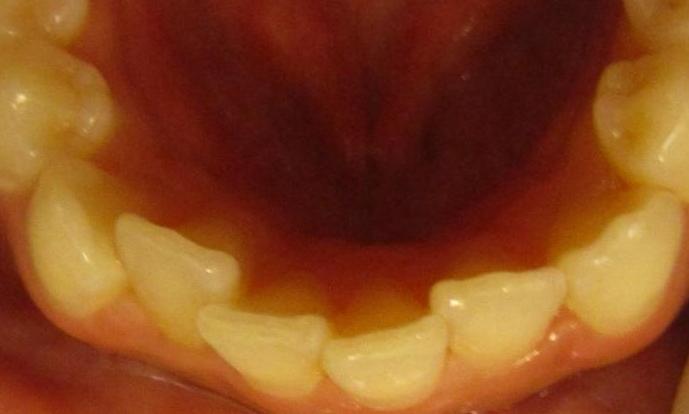

Invisalign was used to correct crowding on the lower teeth.

Before

After